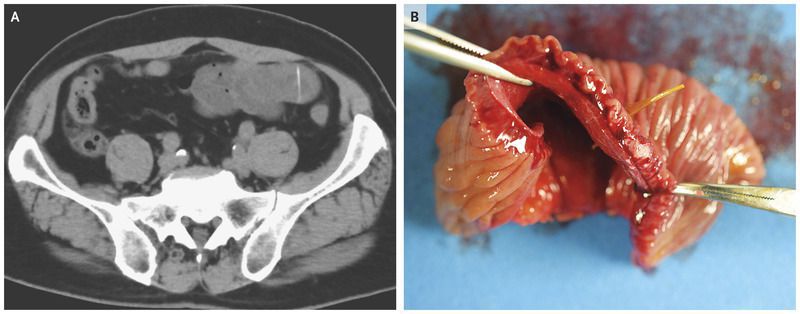

A 73-year-old man presented to the emergency department with the acute onset of severe lower abdominal pain. He recalled eating yellowtail fish the day before the onset of the pain. His temperature was 38°C, blood pressure 122/69 mm Hg, and heart rate 77 beats per minute. On physical examination, he had tenderness across the lower abdomen with rebound tenderness. Laboratory tests showed a white-cell count of 10,300 per cubic millimeter (reference range, 3300 to 8600) with 83% neutrophils. Computed tomography of the abdomen revealed a thickened gut wall and penetration of the small intestine by a linear, high-density body (Panel A). Laparotomy revealed a small-bowel perforation from a fish bone 2 cm in length (Panel B). Small-bowel resection was performed, and the patient received treatment with antibiotic agents. The postoperative course was uncomplicated, and the patient was discharged home on day 8 after surgery.